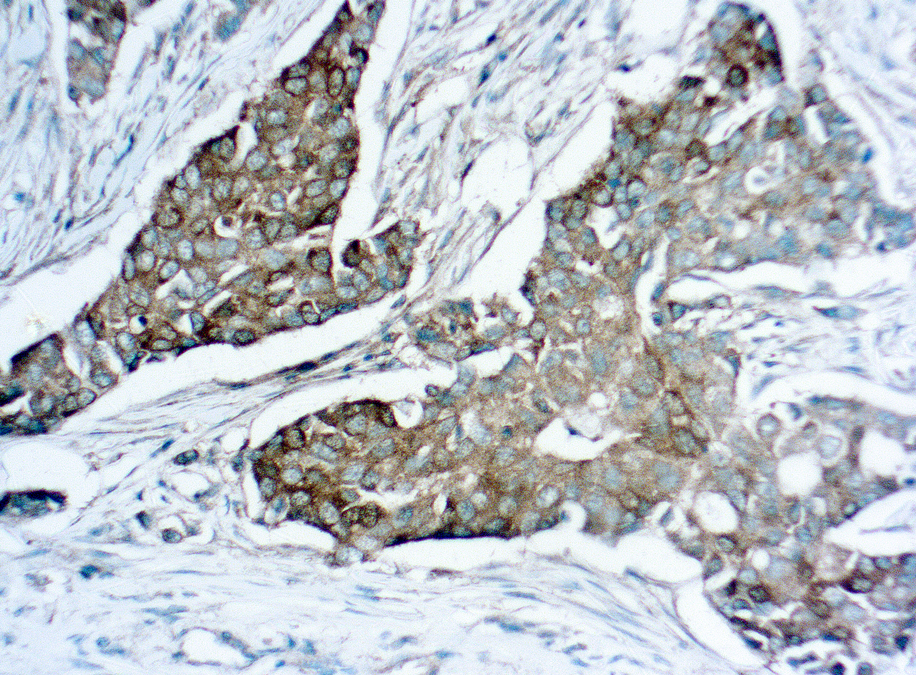

Actin Alpha Smooth Muscle

This antibody is specific to a-smooth muscle isoform of actin. It reacts with smooth muscle cells of vessels and different parenchymes. This antibody does not cross-react with ß and ?-cytoplasmic, a-sarcomeric and a-myocardial actin isoforms.ng paraneoplastic syndromes by secreting ACTH.

Clone 1A4

Application IHC